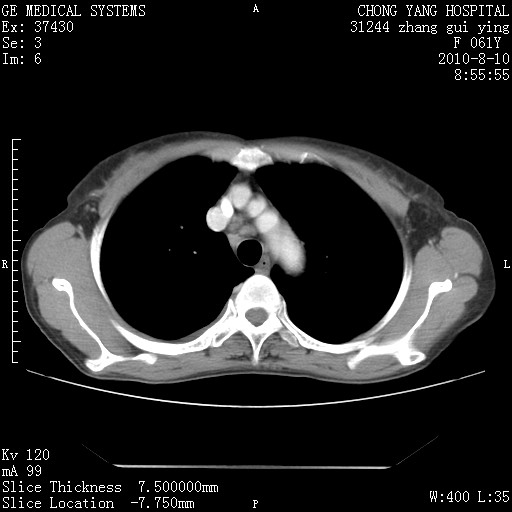

标题: CT28314:F61Y胸部增强,发热咳嗽一周入院,后面的为一周前平 [打印本页]

标题: CT28314:F61Y胸部增强,发热咳嗽一周入院,后面的为一周前平

右肺下叶中心性肺癌可能性大

1、支持考虑右侧中央型肺癌伴右肺中叶节段性不张及下叶支气管黏液痰栓    2、左肺上叶舌段感染。

支持右下肺中央型肺癌并左上肺感染.

支持3楼意见,还要考虑:纵隔及肺门淋巴结转移、右侧少量胸腔积液。

确切的说:1:右肺下叶中心型肺癌侵及中叶支气管并中叶不张,纵膈淋巴结转移。2:左肺舌叶炎症。3:右侧胸腔少量积液

块影平扫32hu,动静脉期62-70hu.

1:右肺下叶中心型肺癌侵及中叶支气管并中叶不张,纵膈淋巴结转移。2:左肺舌叶炎症。3:右侧胸腔少量积液。支持!

考虑右下肺肺癌,纵隔淋巴结转移i。

右肺下叶中心型肺癌侵及中叶支气管并中叶不张,纵膈淋巴结转移。2:左肺舌叶炎症。3:右侧胸腔少量积液